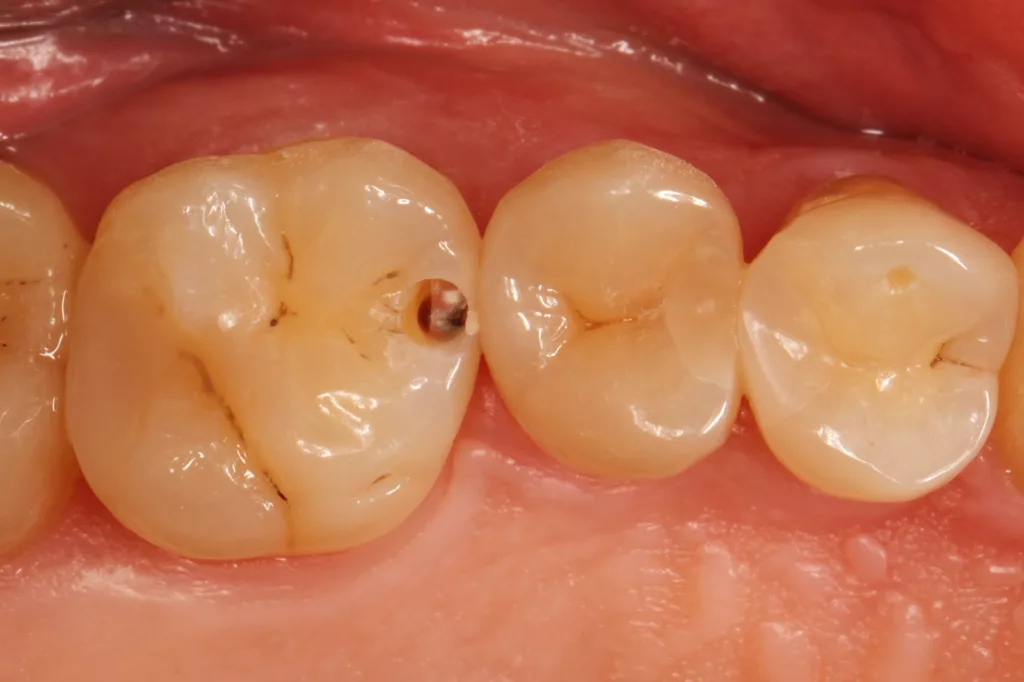

Fall 5: Versorgung einer okklusalen Kavität an einem unteren Molaren

Auch im Molarenbereich können Bulkflow-Materialien effektiv und ökonomisch eingesetzt werden, ohne Abstriche an der Ästhetik machen zu müssen, was der Fall des hier versorgten Zahnes 46 bei einer 22-jährigen Patientin zeigt. Die Abbildung 24 stellt die bereits präparierte und mit einem Einzelzahnkofferdam isolierte Kavität mit der Phosphorsäurekonditionierung der Schmelzränder (Gel Etchant, Kerr) dar. Die Entscheidung zur absoluten Trockenlegung fiel aufgrund der nicht so einfach kontrollierbaren Zunge und der vielen Schluckreflexe, was das Risiko einer ungewollten Speichelkontamination der Klebefläche unverhältnismäßig erhöhte.

Die Verwendung des Kofferdams ist generell eine sehr empfehlenswerte, aber keine zwingende Voraussetzung zur Etablierung einer suffizienten Kontaminationskontrolle [47,96]. Das bisher auch bereits verwendete Zwei-Schritt-Universaladhäsiv G2 Universal wurde hier in der selektiven Schmelzätztechnik angewendet, d.h., das Material arbeitet auf dem Dentin selbstkonditionierend (Abb. 25). Die bislang zu diesem innovativen Mehrflaschen-Universaladhäsiv publizierten Daten zeigen eine beeindruckende Performance, die den Vergleich mit sogenannten Goldstandards [98] wie einem Optibond FL nicht scheuen müssen [13,18,34,58,63,114,119,127,130]. Im nächsten Schritt wurden die einzelnen Höcker mit dem angenehm standfesten Flowable aufgebaut (Abb. 26). Die Abbildung 27 zeigt die komplett versorgte okklusale Kavität, die Abbildung 28 die Situation unmittelbar nach Ausarbeitung und Politur. Erneut beeindruckt die gute Farbadaptation.